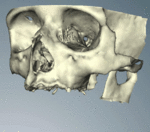

قبل زراعة الأسنان، يطلب من المريض اجراء فحص تصوير للأسنان، وعادة يطلب اجراء صورة خاصة (صورة أشعة بانوراما للأسنان) أو حتى فحص التصوير المقطعي المحوسب (CT)، للكشف والتشخيص عن حالات الأسنان التي ليس بالامكان رؤيتها من خلال الفحص الاعتيادي.

في الحالات التي تكون فيها انسجة عظم الفك غير مناسبة لتقبل الغرسات، يجب القيام بعلاجات مسبقة لعدة اشهر قبل زراعة الاسنان لانشاء منطقة مناسبة في الانسجة لتلقي الغرس (تركيب العظام).